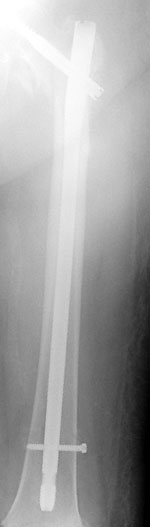

Repair of an intertrochanteric fracture with an intramedullary nail. The nail is in the hollow cavity of the femur (thighbone) rather than on the side of it (as with a plate).

Repair of subtrochanteric fracture with a long intramedullary nail.

Interlocking screws at the end of the nail make the fixation more secure.